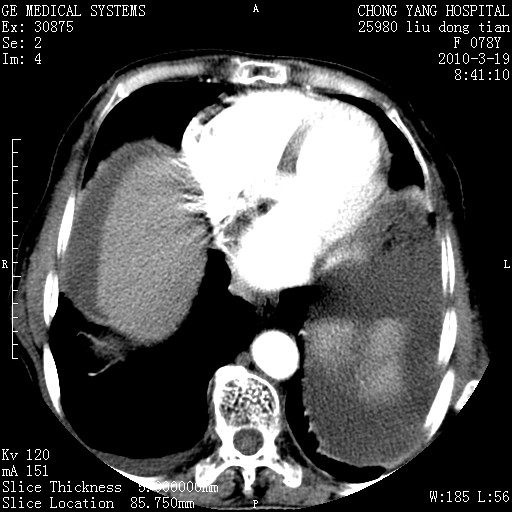

胰头有肿块形成,胰头ca伴肝脾、腹膜腹膜后转移

胆囊有软组织影有强化,支持胆囊癌,肝脾、腹膜后淋巴结转移。

nhl的淋巴结多围绕主动脉,而且主动脉会移位,所以不考虑nhl。

分开来讲:肝左叶、尾叶病灶有不均强化像肝癌;

脾脏病灶无强化,像多发囊肿或淋巴管瘤,不除外淋巴瘤(低强化);

肝门、胰腺头、腹膜后多个团块: 淋巴瘤,转移;

一元论最好了 淋巴瘤所致改变; 胆囊癌转移不像,胆囊周围肝组织清晰,肝癌淋巴结转移?三元论都不止。

胰头ca伴肝脾、腹膜腹膜后转移!

最后报的胰头癌多发转移,脾脏单独考虑囊肿或淋巴管瘤。